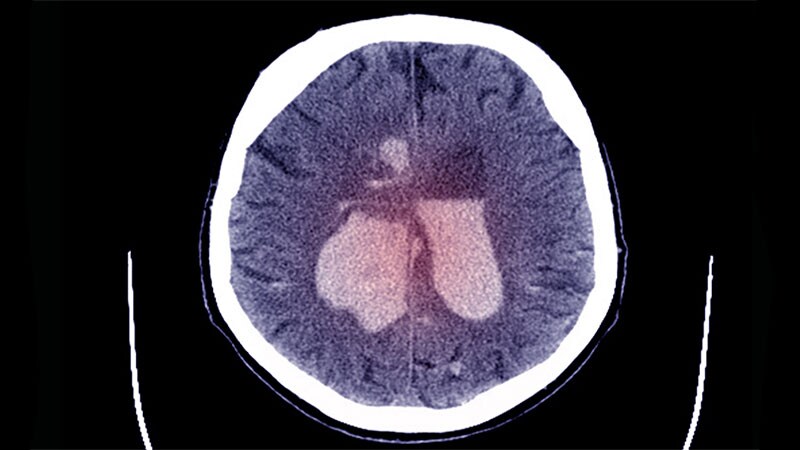

ISC 2023Tirofiban Superior to Aspirin in Stroke Without Large OcclusionAmong patients with disabling strokes without medium or large occlusions, more of those taking tirofiban had good function at 90 days than those on aspirin, results of the RESCUE BT2 trial show.

ISC 2023Thrombectomy Benefits Stroke With Large Core Volumes: SELECT2A new international trial has shown large benefits of thrombectomy in patients with ischemic strokes with a large core volume, which should lead to a change in clinical practice.